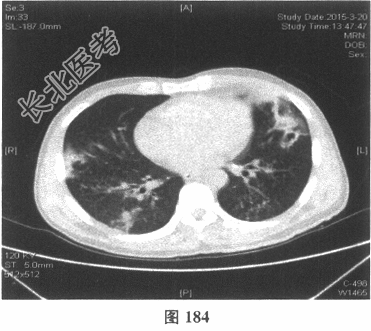

- [材料题] 患者男性,52岁,因间断发热伴咳嗽,咳少许黄痰,无咯血,伴胸闷憋气20余天就诊。体检:体温37.6~38.3℃。既往体健。查体:体温37.6℃,心率83次/分,呼吸20次/分,血压117/64mmHg。神志清,精神可,口唇无发绀;双肺呼吸音粗,可闻及广泛干、湿性啰音,以干啰音为主;心率83次/分,律齐,各瓣膜听诊区未闻及病理性杂音;腹软,无压痛及反跳痛,肠鸣音3次/分,双下肢无水肿。血常规检查:白细胞计数26.32×109/L,中性粒细胞0.846,血红蛋白117g/L,血小板计数1911×109/L;C反应蛋白119.05mg/L。尿常规检查:隐血2(+),蛋白1(+)。痰培养:曲霉菌属,请排除污染。生化全套检查:白蛋白19.6g/L,谷丙转氨酶24.2U/L,谷草转氨酶25.8U/L,γ-谷氨酰基转移酶91.4U/L;尿素氮13.00mmol/L(2.14~7.14mmol/L),肌酐166.8μmol/L(31~132μmol/L);血钾5.6mmol/L。肺部CT见图178~图185。